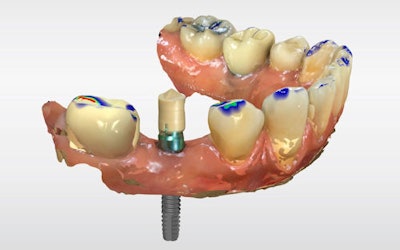

The definitive crown was then designed in CEREC software (Figure 4) using virtual articulation and occlusal analysis (Figure 5) and verified in a full-arch digital view for occlusal harmony (Figure 6). Milling was completed using CEREC Primemill with a Katana Zirconia One for Implant block, producing excellent marginal adaptation and lifelike translucency (Figure 7).

Figure 4: Digital crown design in CEREC software.

Figure 5: Virtual articulation and occlusal analysis.